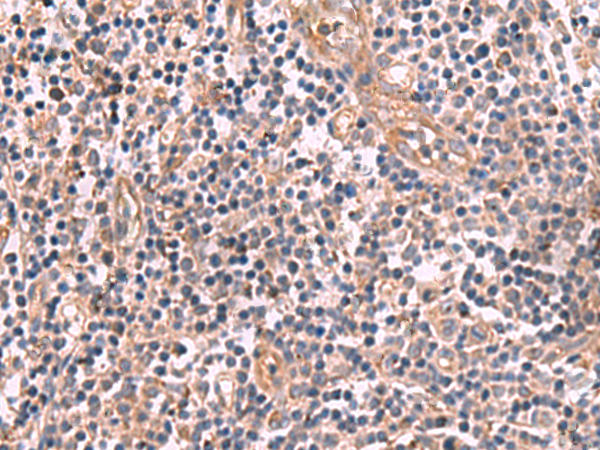

分类: 科研抗体货号: P09829别名: DAP4; THAP0; PRKRIR; P52rIPK应用: IHC反应种属: Human, Mouse